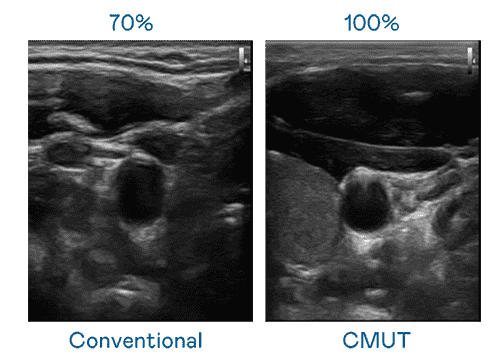

CMUT 技术是一种用电容式微机电元件来产生超音波讯号的技术。。与传统 PZT 压电式技术相比,,CMUT 频宽增加 30%,,,,更宽频的超音波讯号让影像解析度大幅提升,,,是实现高影像品质医疗超音波扫描、、、、促进精准医疗发展的关键技术。。。。

大频宽带来超清晰影像

超音波影像的解析度高低,,首先取决于探头能发出的讯号频宽。。财神娱乐 CMUT 可提供高清晰的超音波讯号,,提供高频宽、、、高灵敏度、、、、影像纹理细节更高的超音波影像,,,,协助医护人员缩短影像判读时间及利用精准的医疗影像进行诊断。。